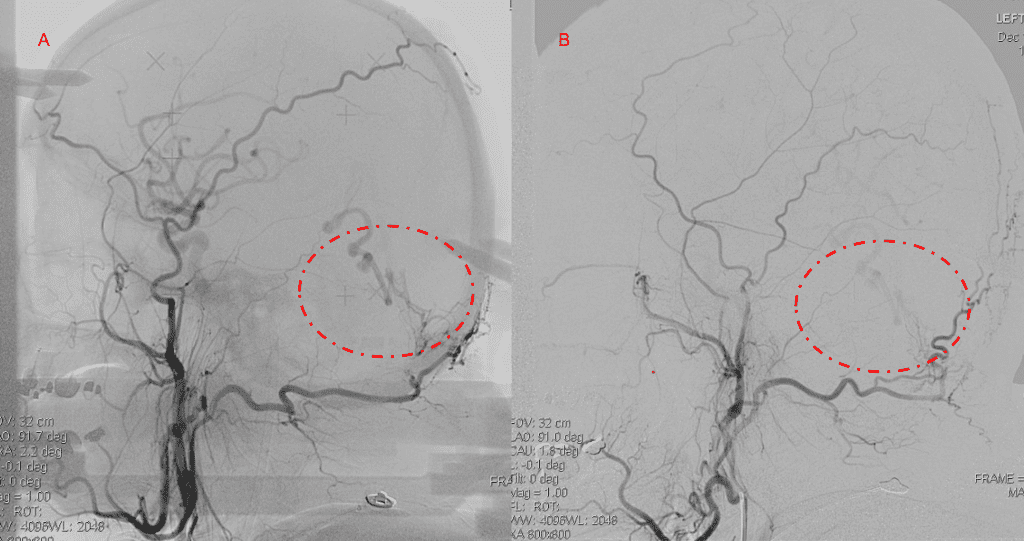

Figure 3. Right ECA AP and Lateral angiograms Pre (A and B) and Post NBCA embolization (C and D) Demonstrate near complete obliteration of right Occipital and Middle Meningeal Artery Fistulas

Figure 4. Left ECA AP and Lateral angiograms Pre (A and B) and Post NBCA embolization (C and D) Demonstrate near complete obliteration of Left Occipital Artery Fistulas.